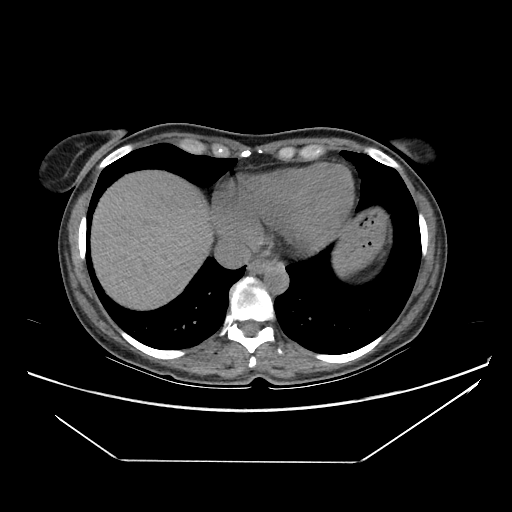

Generated VENOUS CT scan (A→B translation)

No window - Raw intensity values

Lung window (WL -600, WW 1500 β†’ Low βˆ’1350, High +150)

Mediastinum window (WL 40, WW 400 β†’ Low βˆ’160, High +240)